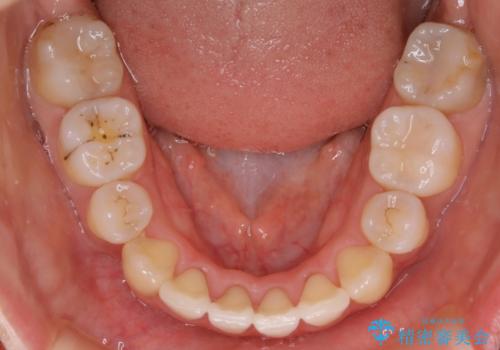

- ワイヤー(審美装置)

- 以前からコンプレックスだった八重歯の治療を主訴にご来院されました。

検査の結果、抜歯をすることでスペースを作って並べる方法が選択され、ワイヤー装置を用いた治療を開始することとなりました。

奥歯の上下のズレ等は軽度で、必要なスペースと抜歯により作られるスペースがほぼ等量だったため治療の単純化が計れ、大きな移動・見た目の劇的な変化に対して比較的早期での治療完了となりました。

叢生の度合いが重く、抜歯が必要なケース。八重歯の部分以外には大きな問題は認められなかったため、劇的変化が起こる治療でも比較的短期間で終了することができました。